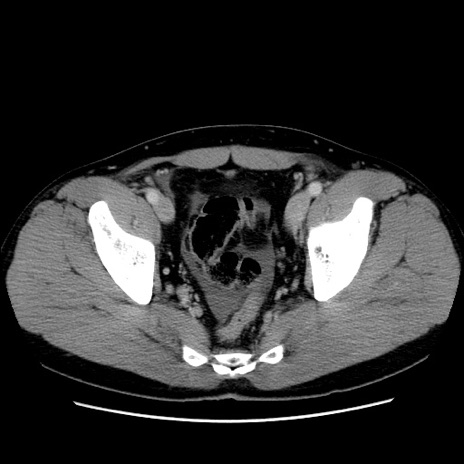

症例4(横断像)

【症例】30歳代男性

【主訴】腹痛、嘔吐

【現病歴】昨晩から突然の腹痛あり、その後嘔吐、軟便も出現。腹痛が改善しないため救急搬送となる。2日前にしめ鯖の食事歴あり。

【身体所見】意識清明、苦悶様、BP 135/90mmHg、BT 35.7℃、腹部:平坦、やや硬、心窩部〜臍部に自発痛、圧痛あり、筋性防御+、反跳痛-

【データ】WBC 8100、CRP 0.57